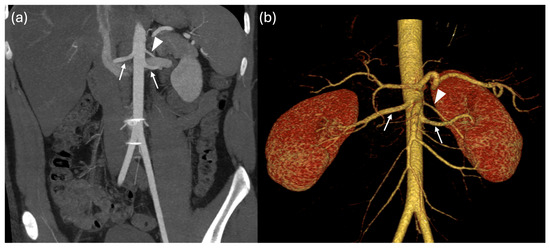

Multiple Renal Arteries as a Potential Contributor to Hypertension in Children and Young Adults

Background: Arterial hypertension in childhood is an increasing health concern, often associated with structural and functional cardiovascular or renal alterations. This study aimed to investigate the prevalence and type of non-stenotic renal artery anatomical variants in children with systemic hypertension and to assess their possible association with cardiac involvement. Methods: A total of 107 children and adolescents with hypertension (mean age 15.4 ± 2.7 years) were evaluated. Hypertension was defined as blood pressure persistently above the 95th percentile for over one year, confirmed by 24 h ambulatory blood pressure monitoring. Patients with known secondary causes were excluded. All underwent renal vascular imaging by CT or MRI and echocardiographic assessment of left ventricular morphology and function. Results: Renal artery anatomical variants were found in 69 of 107 patients (65%), mainly unilateral or bilateral accessory polar arteries. Other anomalies found (left renal vein narrowing or duplication, severe left renal artery stenosis) were excluded from the statistical analysis. Normal renal vasculature was observed in only 32%. Left ventricular hypertrophy was detected in 41%, highlighting a significant prevalence of target-organ involvement. No statistically significant differences were found in terms of hypertension or hypertrophy between patients with renal artery anatomical variants and those without. However, patients with renal anomalies more frequently required dual antihypertensive therapy (p = 0.025). Conclusions: Renal artery anatomical variants, even in the absence of overt stenosis, may contribute to the pathogenesis of pediatric hypertension and complicate its management. Systematic evaluation of renal vasculature should be considered in the diagnostic workup to improve risk stratification and guide management strategies.